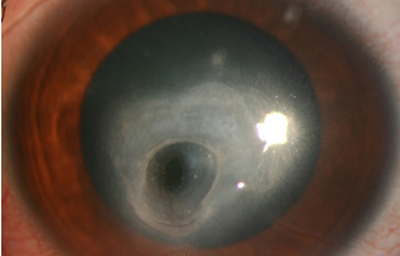

Superficie corneal irregular y grisácea, (Fig. 1, 2) con opácidades granulares en parche y formación de líneas epiteliales elevadas de aspecto granular (Fig. 3), que pueden arborizar dando imágenes de pseudodendritas. Opacidades superficiales satélites. (Figura 4) Inyección ciliar. Ulceración epitelial variante. (Figura 5).

Fig. 3 Líneas epiteliales elevadas. Síntomas de 40 días evolución